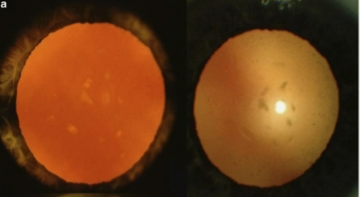

mature cataract

opaque cortex w/ intact capsule

hypermature cataract

liquefication of lens fibers w/ leakage of H2O & protein